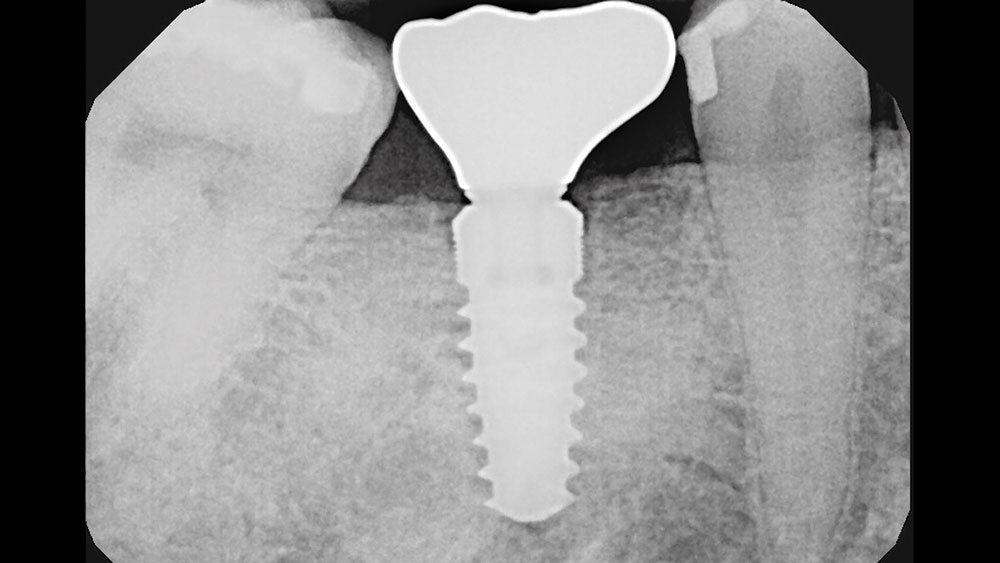

cm1401-rd-corner-efficacy-hahn-tapered-system-1a

cm1401-rd-corner-efficacy-hahn-tapered-system-1b

Figures 1a, 1b: Calibration of the bone loss measurements was determined by measuring the length of the implant (1a), or by measuring the diameter in cases where the implant apex was not visible (1b).